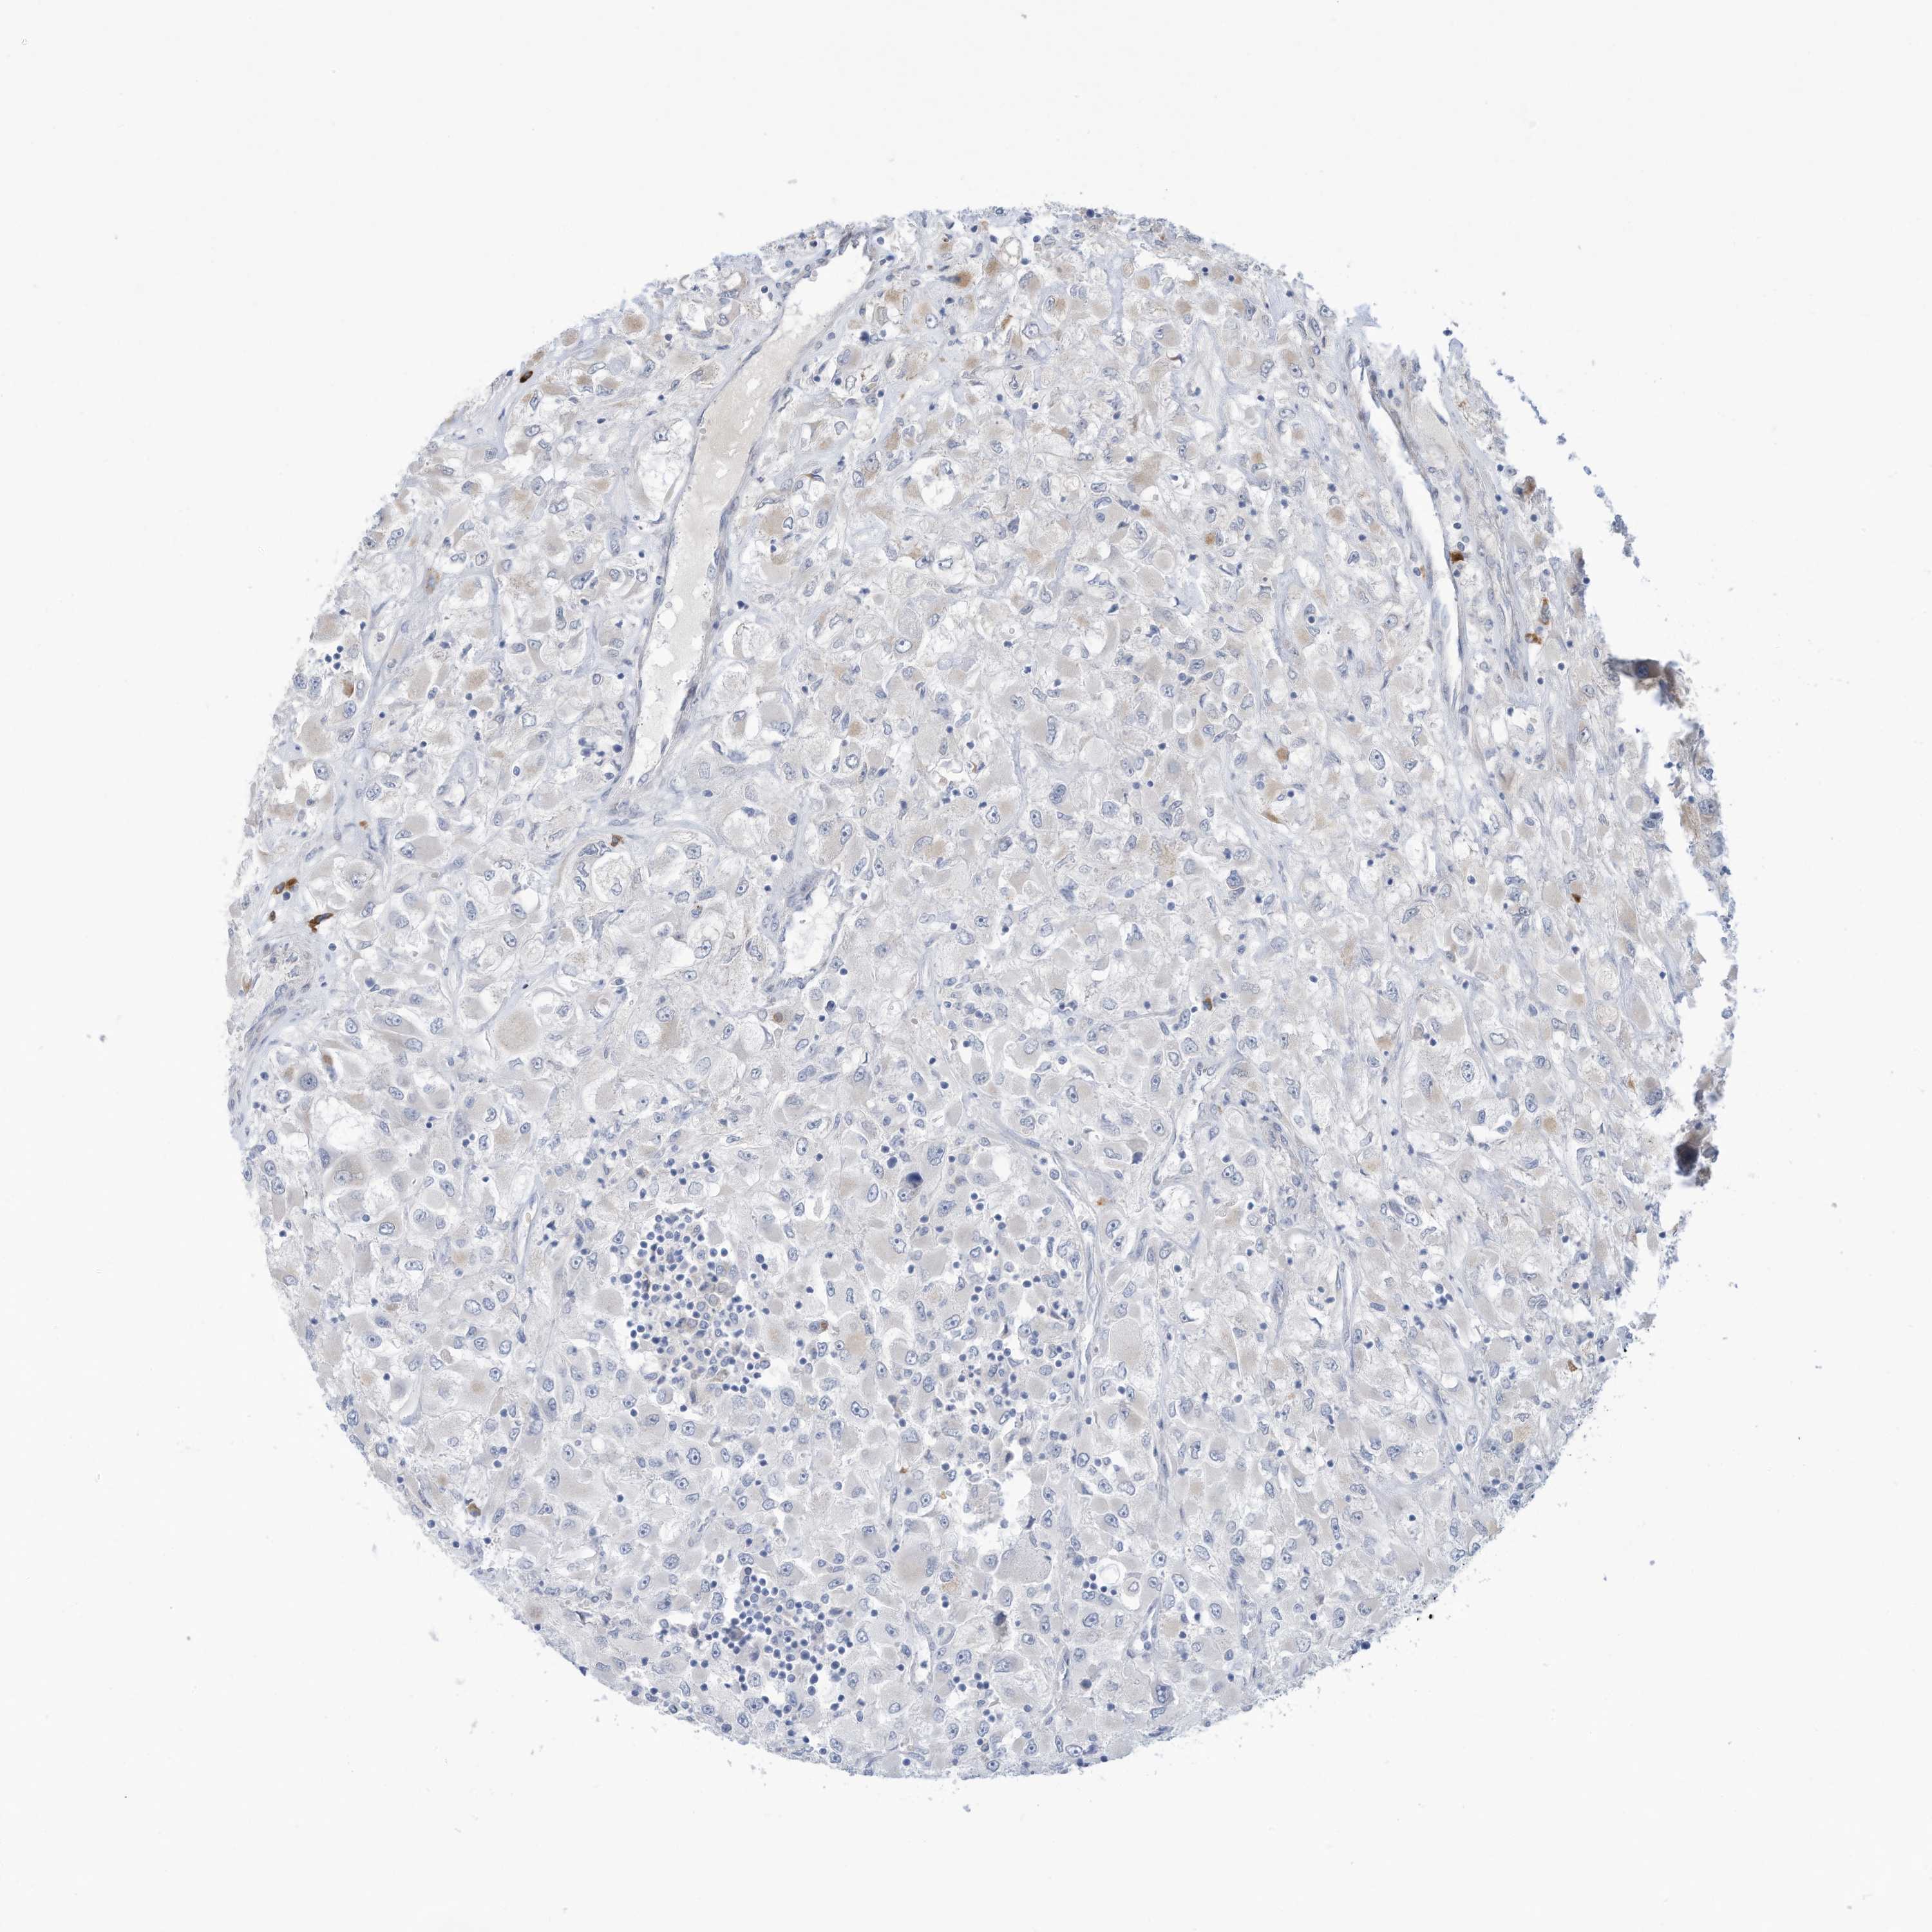

KIDNEY RENAL PAPILLARY CELL CARCINOMA (TCGA) - Interactive survival scatter ploti

The Survival Scatter plot shows the clinical status (i.e. dead or alive) for all individuals in the patient cohort, based on the same data that underlies the corresponding Kaplan-Meier plots. Patients that are alive at last time for follow-up are shown in blue and patients who have died during the study are shown in red.

The x-axis shows the expression levels (FPKM) of the investigated gene in the tumor tissue at the time of diagnosis. The y-axis shows the follow-up time after diagnosis (years). Both axes are complimented with kernel density curves demonstrating the data density over the axes. The top density plot shows the expression levels (FPKM) distribution among dead (red) and alive patients (blue). The right density plot shows the data density of the survived years of dead patients with high and low expression levels respectively, stratified using the cutoff indicated by the vertical dashed line through the Survival Scatter plot. This cutoff is automatically defined based on the FPKM cutoff that minimizes the p-score. The cutoff can be changed by dragging the vertical line or by entering a cutoff value in the square labeled "Current cut-off".

Under the Survival Scatter plot the p-score landscape (black curve; left axis) is shown together with dead median separation (red curve; right axis). Dead median separation is the difference in median mRNA expression between patients who have died with high and low expression, respectively. It is calculated as follows: median FPKM expression of dead patients with high expression - median FPKM expression of dead patients with low expression. This is intended to aid the user in visually exploring custom cutoffs and the associated p-scores and dead median separation.

Individual patient data is displayed and can be filtered by clicking on one or more of the category buttons on the top of the page. Categories describing expression level and patient information include: high, low, alive, dead, female, male and tumor stages. The scale of the x-axis can be toggled between linear and log-scale by clicking on the "x log" button. Mouse-over function shows TCGA ID, patient information and mRNA expression (FPKM) for each patient.

& Survival analysisi

Kaplan-Meier plots summarize results from analysis of correlation between mRNA expression level and patient survival. Patients were divided based on level of expression into one of the two groups "low" (under cut off) or "high" (over cut off). X-axis shows time for survival (years) and y-axis shows the probability of survival, where 1.0 corresponds to 100 percent.

ZNF292 is not prognostic in Kidney Renal Papillary Cell Carcinoma (TCGA)